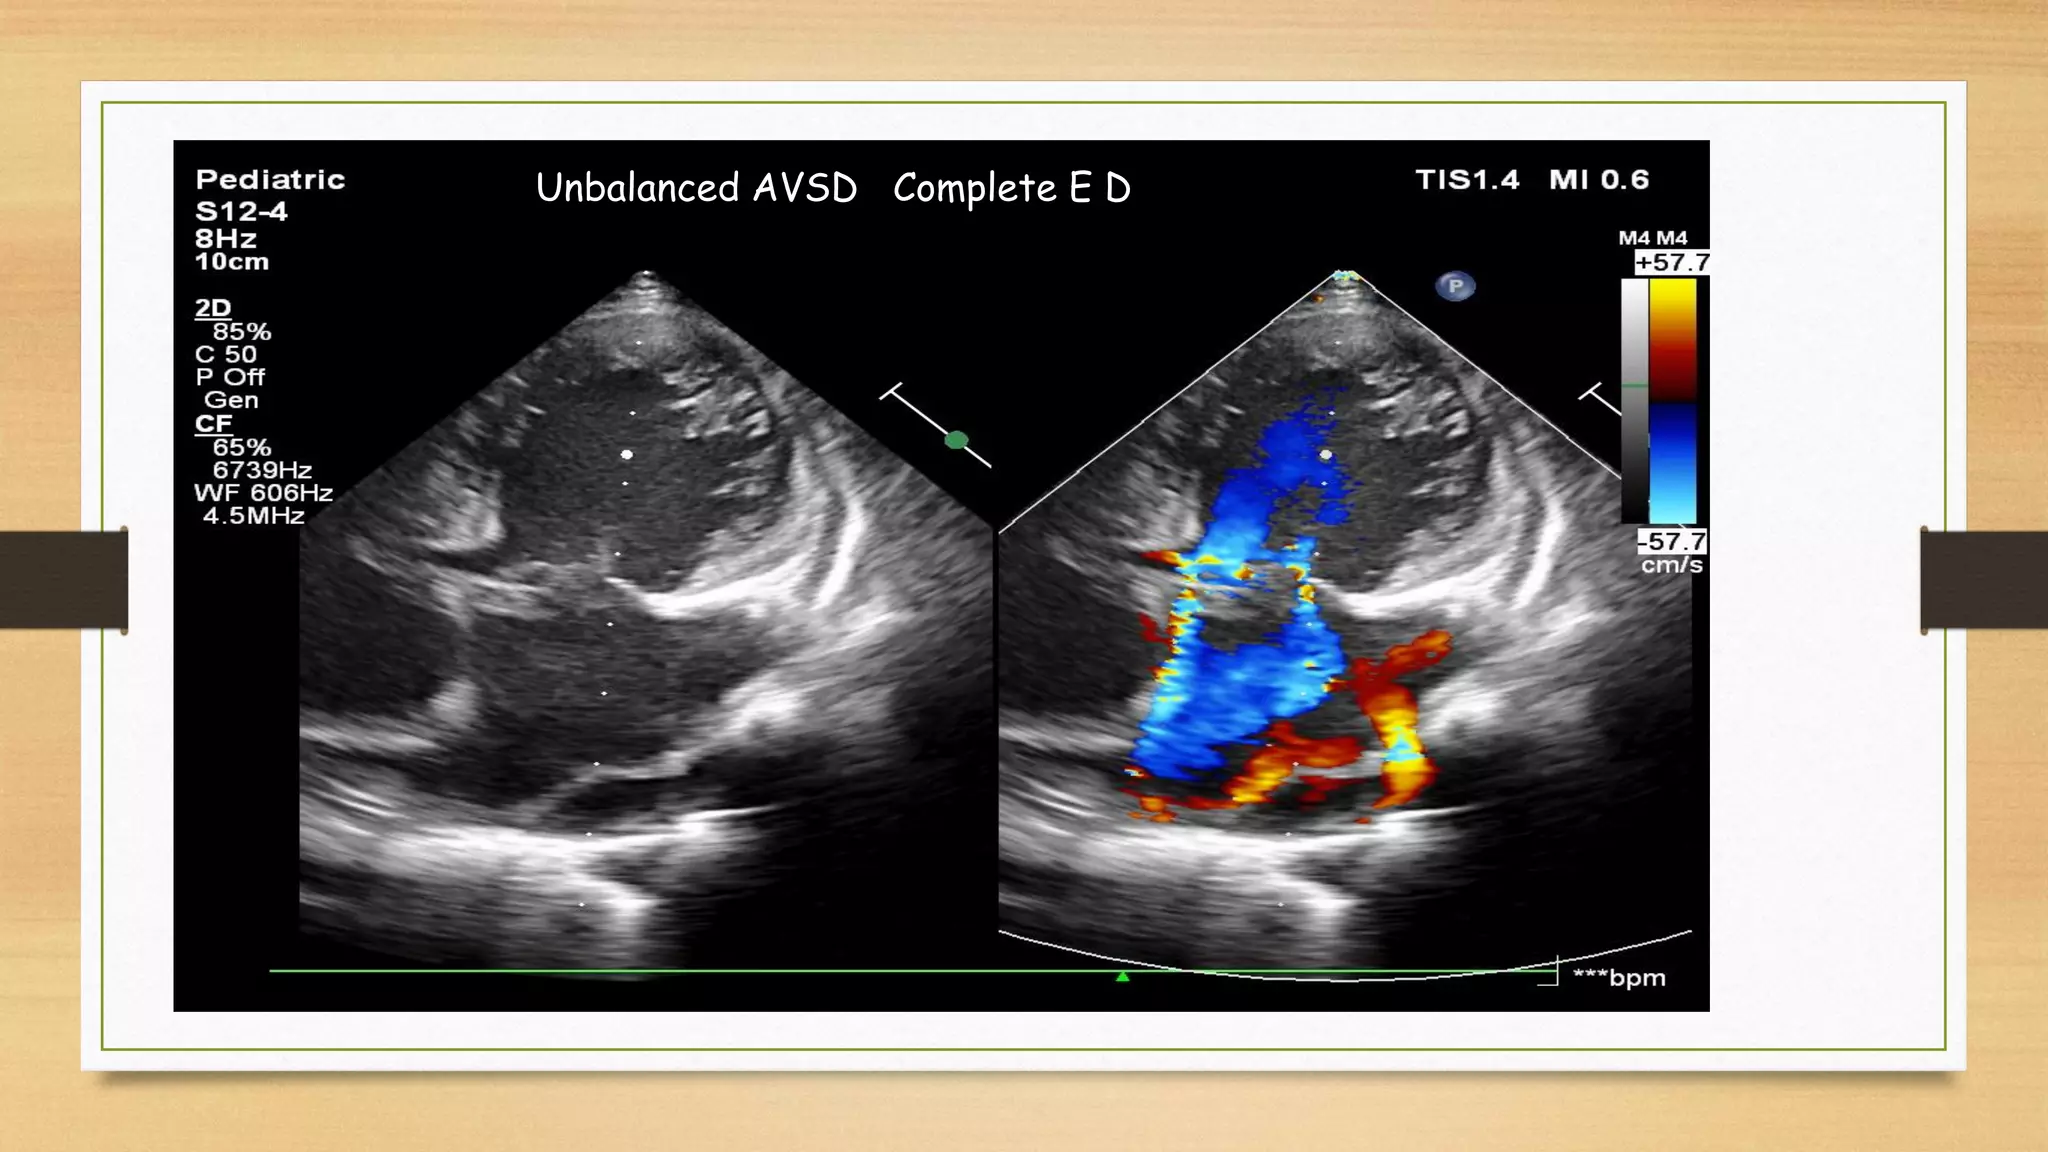

Unbalanced AVSD Complete E D

b. Unbalanced AVSD: One of the ventricular chambers is hypoplastic. This form is usually

associated with complex congenital defects such as heterotaxy syndrome (isomerism).

2/3 RV dominant, LV hypoplastic, HLHS, CoA

1/3 LV dominant, RV hypoplastic, Down syndrome

THE CONCEPT OF BALANCE

Both partial and complete AVSD can be either “balanced” or “unbalanced” based on how the AV

junction is shared by the ventricles. If the AV inlet is equally shared by the two ventricular

chambers, then this is consistent with a balanced AVSD. In an unbalanced AVSD, one ventricle is

hypoplastic compared with the other. The larger ventricle is termed the “dominant” ventricle. For

example, unbalanced AVSD with right ventricular (RV) dominance has a hypoplastic left ventricle

with more than half of the AV junction committed to the right ventricle. RV dominance is

associated with coarctation of the aorta and other arch anomalies. In contrast, unbalanced AVSD

with LV dominance has a hypoplastic right ventricle and is associated with pulmonary stenosis or

atresia. Unbalanced AVSD occurs in 10% to 15% of all AVSDs and two-thirds are RV dominant